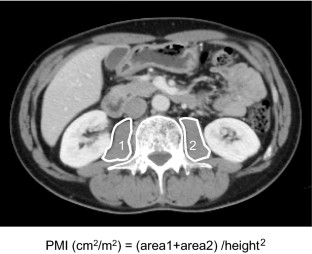

Included in this study were 113 ESCC patients who underwent NACRT followed by esophagectomy. PMI and prognostic markers were measured at their initial visit, just before surgery (after NACRT), and 3 months postoperatively.

Fig. 1